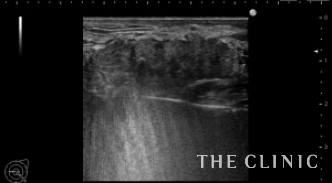

エコー所見です。 オイルシストの下に5㎝を超える混合性のしこりを認めます。(左)

他にもオイルシストが多発していました。